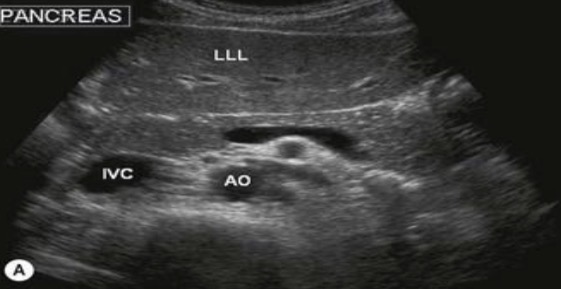

Posterior vascular landmarks for pancreas

IVC and aorta

Pancreas echogenicity to the liver

Isoechoic or hyperechoic to the liver

Normal anatomy of pancreas

Dumbbell or sausage shaped